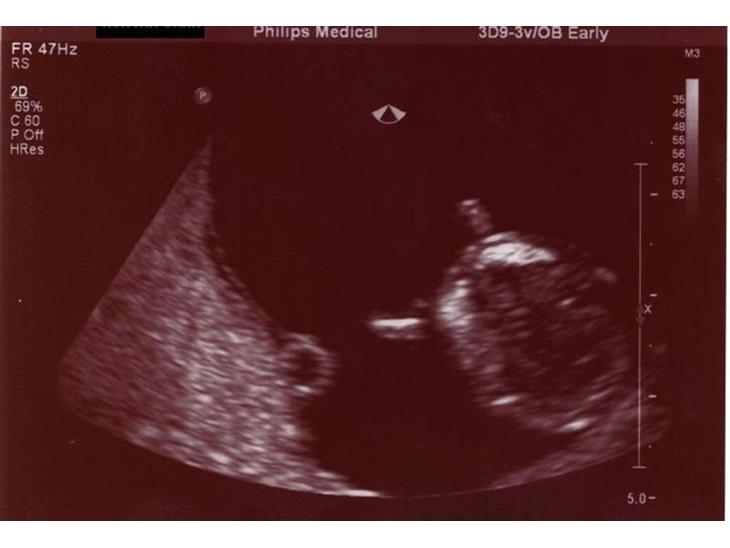

Nakkefoldsscanningen Onsdag den 21/1/07

Første billeder af blyppen